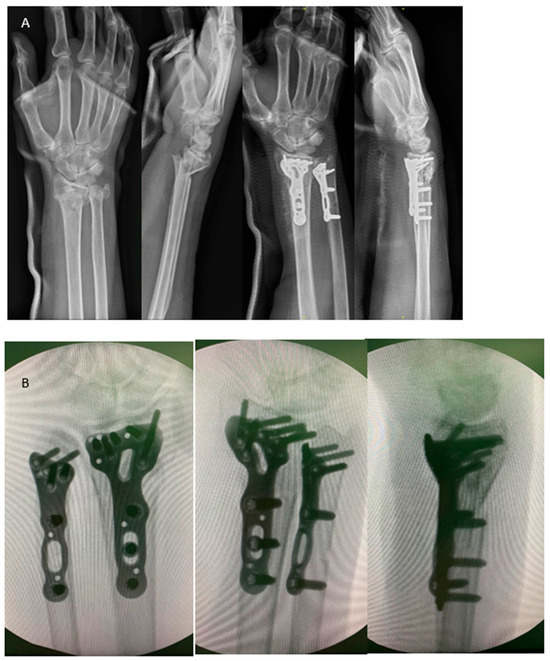

Figure 2.

(A) A sixty-seven-year-old woman sustained a distal forearm fracture. She underwent ORIF to both bones via the modified dual channel approach. The figure shows anteroposterior/lateral view at initial and postoperative day 1. (B) Ensure the locking plate placement on the ulna does not extend beyond the radius sigmoid notch to avoid impingement. The three intraoperative fluoroscopic images, respectively, represent the AP view, PA view, and lateral view, which may help us identify the plate positioning and avoid screw intra-articular penetration.